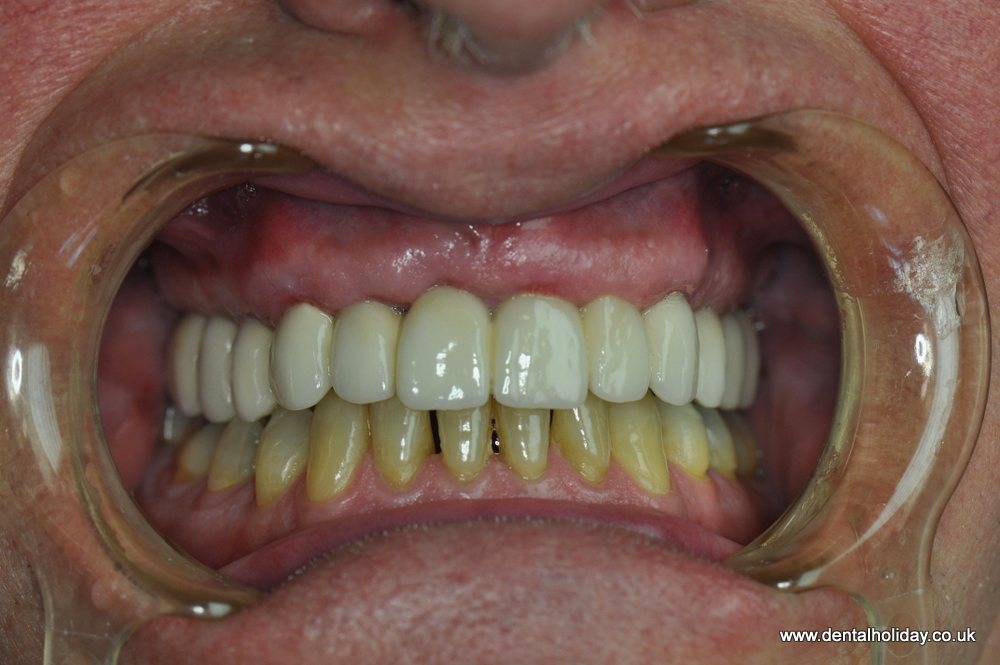

After his initial dental consultation done on the day of his 1st visit to us, our implantologist Dr. Marek prepared a personalized treatment plan for John, which included a 12 unit ceramic bridge fitted on 5 dental implants.

Here’s John with his new final smile: